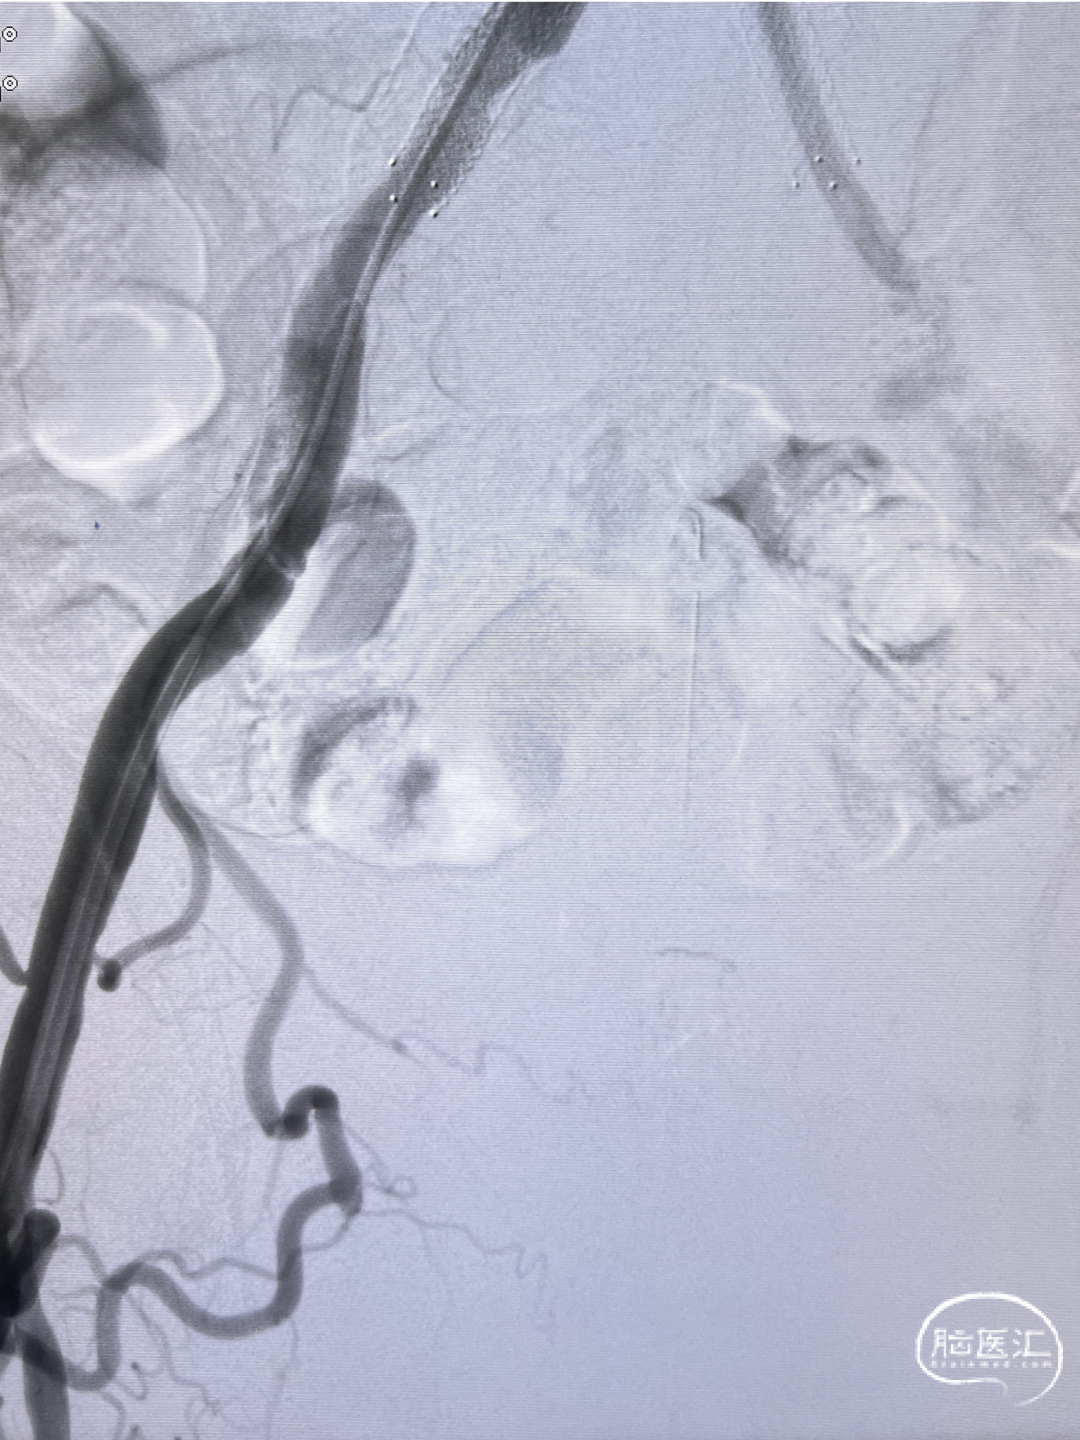

双侧股动脉造影:双侧髂动脉支架迂曲,不能通过造影导管及导丝。

经桡入路完成全脑血管造影:主动脉弓。

右侧颈内动脉闭塞。

左侧颈内动脉重度狭窄,左侧大脑中动脉闭塞,通过前交通动脉向右侧大脑中动脉供血区代偿。